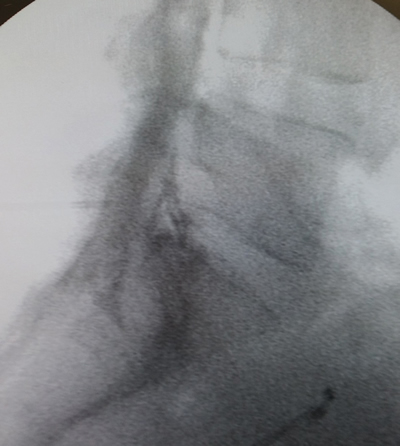

Tablas y Figuras

Figura 1